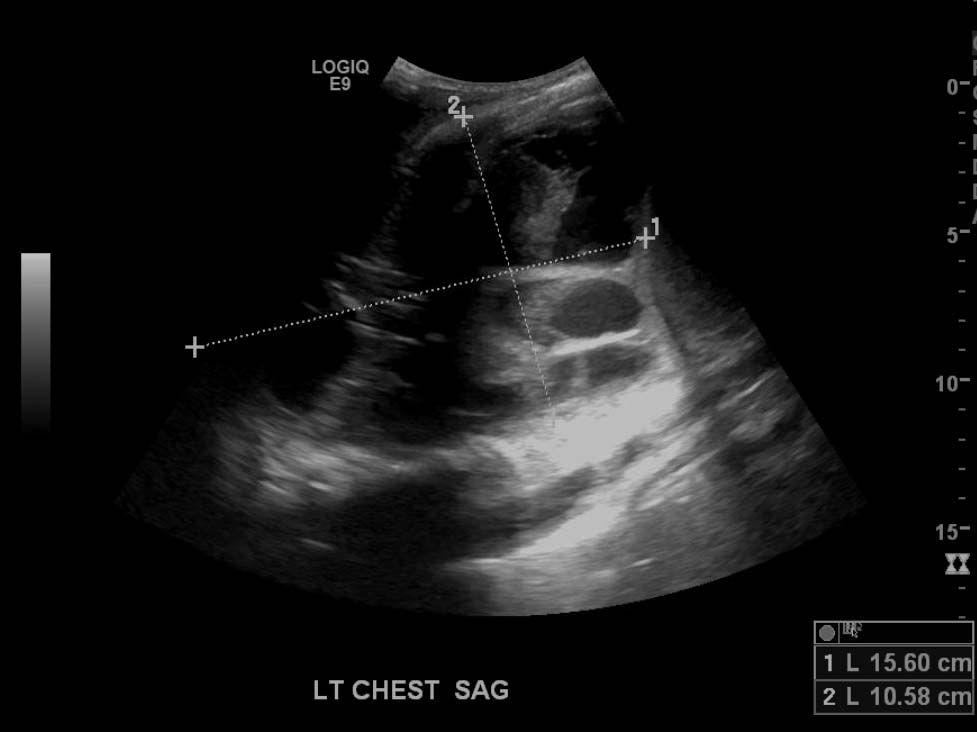

- Large, complex, multiseptated left pleural fluid collection

- Adjacent airspace consolidation in the left lung with air bronchograms

Large, complex, multiseptated left pleural fluid collection with adjacent airspace consolidation, concerning for pneumonia and empyema. No discernible right pleural effusion.

- As the lung fills with fluid, the only remaining air is in the bronchi, which produces air bronchograms – these appear as punctate and linear echogenic foci within the lung (see annotated image #3)

- Also, when densely consolidated, the lung becomes more discretely visible and takes a liver-like appearance, referred to as “hepatization”

- Pneumonia is an airspace filling process, so the size of the hepatized lung relative to the adjacent pleural fluid collection is often larger in pneumonia than in atelectasis